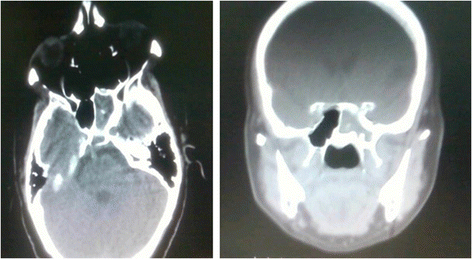

A complete head and neck examination was unremarkable aside from a lateral rectus palsy present in the right eye. Computerized tomography scanning (CT) of the paranasal sinuses revealed opacification with hypertrophic mucosa and secretions in the left sphenoid sinus (Figure 1).

Fortunately, the patient in this case was able to pay for a CT scan which showed opacification in the left sphenoid sinus with hypertrophic mucosa and secretions, consistent with acute or chronic sinusitis, a mucous retention cyst, polyp or mucocele [7,19]. An MRI would have been ideal to rule out cavernous sinus involvement as the etiology for the contralateral abducens nerve palsy, however this was not financially possible for the patient.